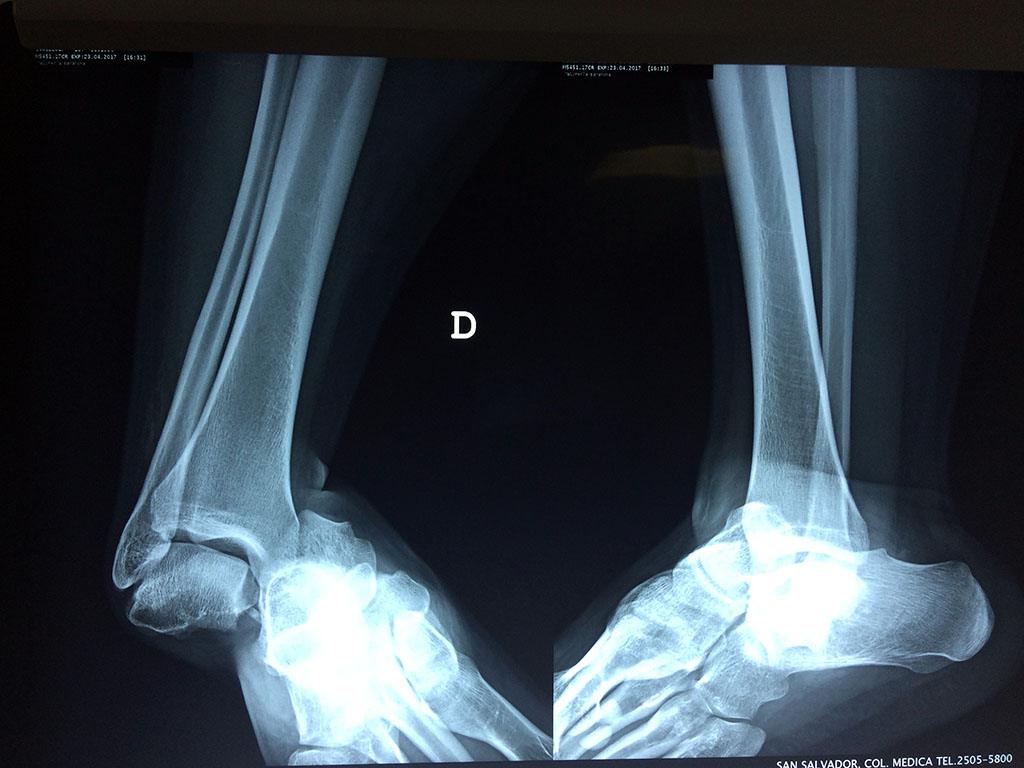

Una fractura de tobillo es la rotura de uno o más de los huesos del tobillo. Estas fracturas pueden ser:

- Completas (el hueso está perforado y está en 2 partes).

- Producirse en uno o ambos lados del tobillo.

- Los extremos de los huesos están desalineados entre sí (desplazados).

- La fractura se extiende hasta la articulación del tobillo (fractura intra-articular).

Cuando se necesita cirugía, es probable que esta implique el uso de clavijas de metal, tornillos o placas para sostener los huesos en su lugar mientras la fractura se consolida. Los elementos de soporte pueden ser temporales o permanentes.